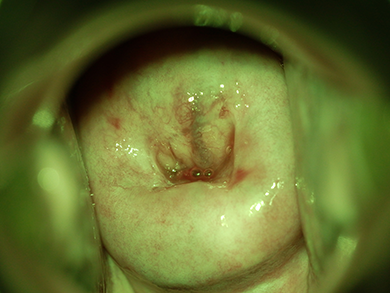

ワンシャッターで 通常光/グリーン光/偏光

ワンシャッターで通常光/グリーン光/偏光の3種類の画像が撮影可能です。

通常光

白色のライトを当てて、単純診を行うことができます。